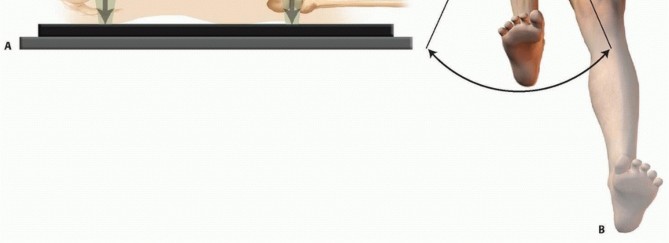

Nail lengths are often determined intraoperatively but can be ascertained by imaging the contralateral femur. Radiographs are evaluated to determine the location and morphology of the fracture; they should be scrutinized for nondisplaced secondary fracture lines that could become displaced during operative treatment. Occasionally, fracture fragments may be stuck in the canal and may need to be pulled out. In the case of fractures that show significant shortening preoperatively, it may be difficult to restore length off the fracture table. A trial reduction should be performed under fluoroscopy before the start of the procedure; the patient must be paralyzed for the procedure. If length is difficult to restore manually, then a femoral distractor should be used for the procedure. Placement of the femoral distractor is described in the section on Fracture Reduction. Before preparing and draping the injured limb, the surgeon should examine the contralateral extremity to determine the patient's normal leg length and rotation. Femoral length can be evaluated by using a radiographic ruler and intraoperative fluoroscopy ( FIG 7A). Normal rotation can be determined by flexing the hip and knee and checking the patient's normal internal and external rotation of the hip and by examining the normal resting position of the foot as the patient lies supine on the operating room table ( FIG 7B).  ---

---  ### FIG 7 • A. Schematic lateral view of a patient on a radiolucent operating room table, depicting how to use a radiopaque ruler and fluoroscopy to determine femoral length. B. Schematic anterior view of a patient on the operating room with the uninjured hip and knee flexed, checking the patient's normal internal and external rotation of the hip.

### FIG 7 • A. Schematic lateral view of a patient on a radiolucent operating room table, depicting how to use a radiopaque ruler and fluoroscopy to determine femoral length. B. Schematic anterior view of a patient on the operating room with the uninjured hip and knee flexed, checking the patient's normal internal and external rotation of the hip.